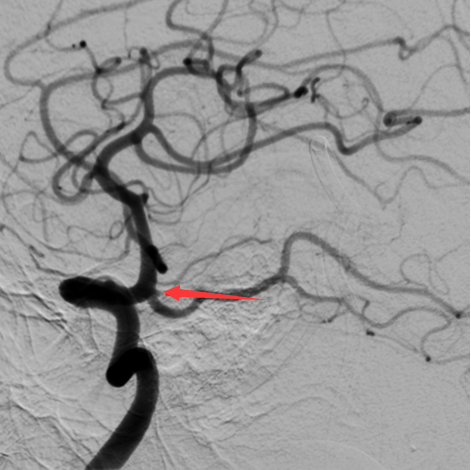

通过脑血管造影检查,罗俊杰在她颅内血管交叉处,发现2枚仅1毫米的微小动脉瘤,科室讨论后认为,后交通动脉瘤出血可能性极大,若短期内再次出血将直接威胁患者生命。

箭头所指为患者病灶处,动脉瘤大小仅1毫米,在造影上几乎微不可见。